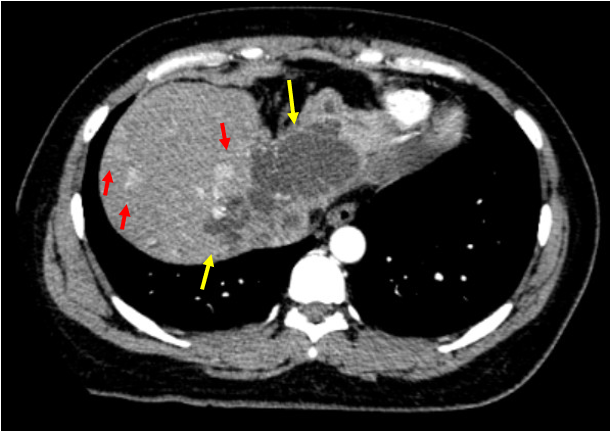

- Chụp cắt lớp vi tính ngực, bụng (có tiêm thuốc cản quang) (17/11):

+ Bụng: Hình ảnh nốt ngấm thuốc gan phải, đường kính 20 mm, ngấm thuốc mạnh thì động mạch, không rõ thải thuốc thì tĩnh mạch. Giãn đường mật hai bên. Xơ gan. Hạch vùng rốn gan và cạnh động mạch chủ (Hình 1).

Hình 1. Hình ảnh các nốt ngấm thuốc (mũi tên đỏ) và giãn đường mật (mũi tên vàng).

+ Ngực: Không phát hiện tổn thương bất thường.